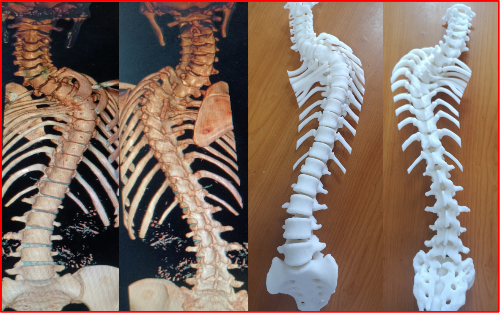

图一 术前三维CT重建及3D模型打印显示上胸椎严重僵硬型先天性脊柱侧凸,多节段分节不全及并肋